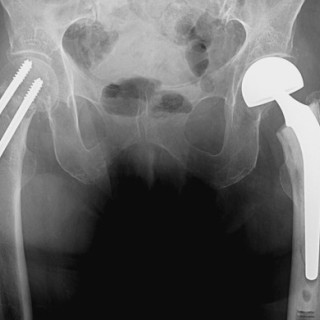

Artrose er sykdom i et synovialt ledd. Det synoviale leddet er et organ bestående av leddbrusk, subkondralt bein og en leddkapsel, som på innsiden er kledd med synovialmembran og på utsiden er forsterket av ligamenter. Sykdommer som primært rammer én av komponentene i et ledd, vil etter hvert medføre sekundære forandringer i de øvrige (fig 1), og det utvikles en leddsvikt som gir pasienten smerter og nedsatt funksjon. Alle ledd kan rammes, men artrose er vanligst i hånd, hofte og kne. Det følgende er en oversikt over epidemiologiske og patologiske forhold, årsaksmekanismer, utredning og...